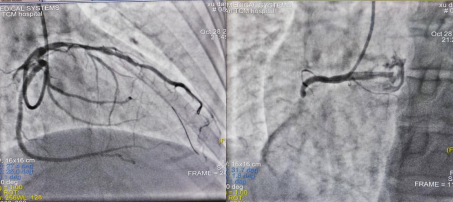

患者刘先生于10月28日20:40饮酒后出现胸痛不适,伴周身汗出,就诊于当地医院,行心电图提示前壁导联ST段抬高,病情危重,当地医院立即与我院院前急救中心联系,并将患者病情及心电图发到我院胸痛中心群,心血管内一科陈传俊医生依据信息提示,考虑患者为急性前壁ST段抬高型心梗,立即指导医生给予急救处置,开启“双绕”绿色通道,快速恢复患者三级血流,患者症状明显缓解,生命体征平稳,转入心血管内一科病房进行后续治疗。

图1 术前造影图2 术后造影